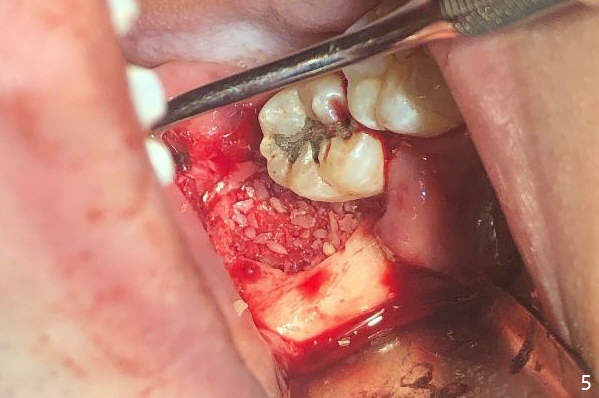

A 22-year-old man with poor oral hygiene requests extraction of the lower right 3rd molar. The buccal gingiva of the 2nd molar is erythematous and edematous (Fig.1 *). There is tenderness between #31 and 32 with severe bone loss (Fig.2 *). After extraction and debridement (Fig.3), Osteogen plug is inserted into radicular portion of the socket (Fig.4 white outline), while allograft is placed coronally (Fig.5, 7), covered by Collagen plug (Fig.6) before suturing. The bone fills the whole socket 1 year postop (Fig.8); there is no root surface exposure at #31. The bone fills the whole socket of #32 one year postop (Fig.8); there is no root surface exposure at #31.